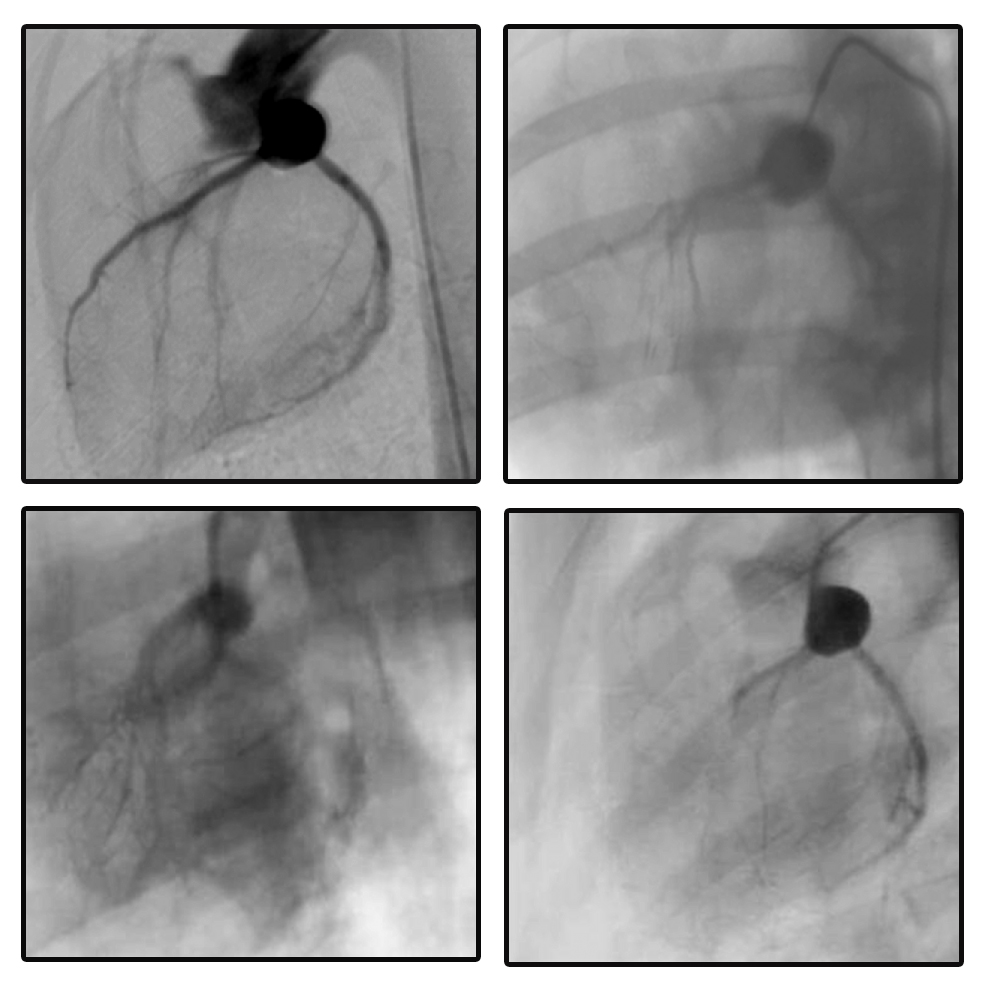

术后8 周各组小型猪冠脉造影检查显示,正常对照组小型猪血管分布清晰可见,冠状动脉LAD可显影,三组手术组LAD约近中1/3处闭塞,闭塞远端血管不显影。rAAV-GFP组有少量的侧支循环建立,rAAV-CD151组侧支循环形成丰富,0~3级均有,形成密度增高的侧支循环网,侧枝循环明显多于rAAV-GFP组。而rAAV-anti-CD151组有极少的侧支血管形成或无侧支循环建立。见图3。

A-正常对照组;B-rAAV-GFP组;C-rAAV-CD151组;D-rAAV-anti-CD151组

图3四组小型猪冠状动脉造影检查

Fig 3Coronary angiography of swines in four groups